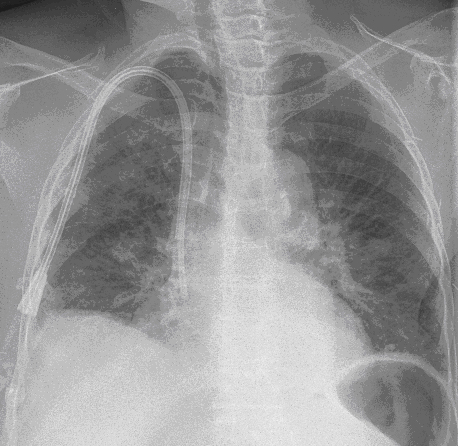

Figure 1: Posterior-anterior (PA) chest radiograph on admission showed interstitial changes and mild air space opacities which were more prominent on the right.